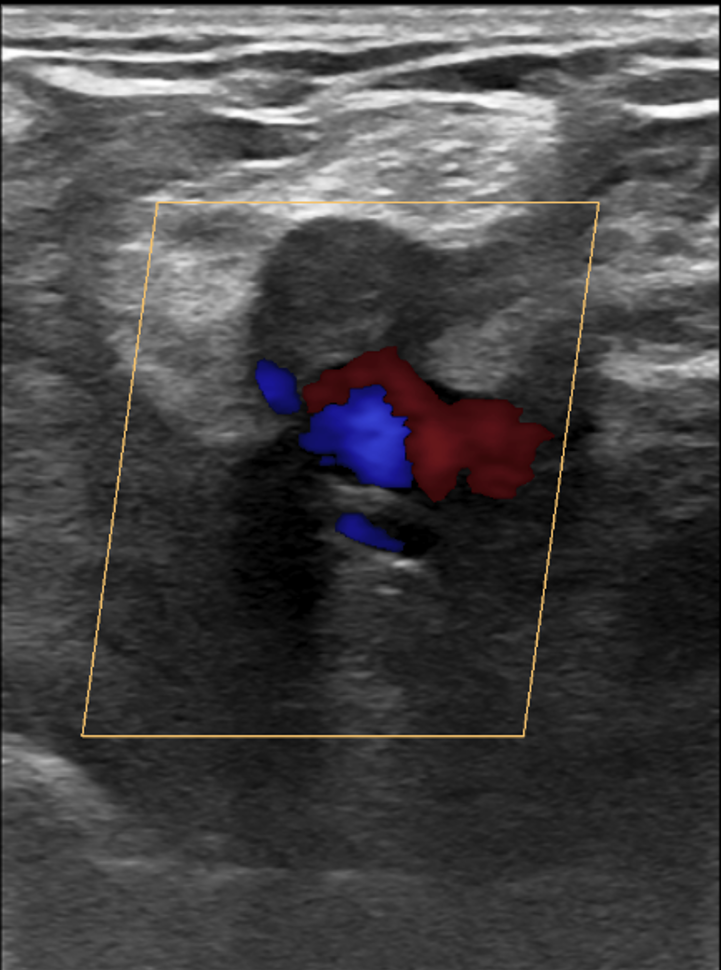

Eco-Doppler de los miembros inferiores (CON comprensión externa) en la fosa poplítea.